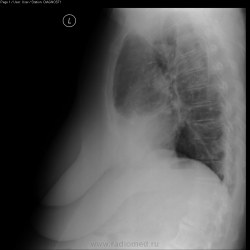

Женщина поступила в пульмонологическое отделение 14.10.2010 с жалобами на одышку, субфебрильную температуру в течние 2 недель, кашель с небольшим колчиеством слизстой мокроты. На момент поступления лейкоцитоз до 12х10`6, c небольшим палочкоядерным сдвигом. СОЭ - до 35

На момент 2-й рентгенографии (21.10.2010) - анализы в норме, кроме СОЭ (~30). Кашель субъективно стал меньше.

Что бы Вы думали по данным рентгенограмам и какая была бы ваша дальнейшая тактика.

Пневмония в S10 слева разрешилась, корни - не очень (лимфоузлы - сомневаюсь), справа в кардио-диафрагмальном синусе - интересные "спайки?" По возможности (и при наличие жалоб - как понял, самочувствие улучшилось) сделать бы КТ (если не жалко)...

В смысле, избыточная жировая клетчатка в левом кардио-диафрагмальном углу. Либо, менее вероятно, но всё же - осумкованный выпот.

Кстати, абдомино-медиастинальная липома - вероятна справа (левый кардиодиафрагмальный синус как раз "остренький").

Совсем забыл про исследование что выложил :) Вообщим, прямоугольная тень в проекции сердца - это хорошо развитая жировая клетчатка (причем развита с обеих сторон, чуть больше слева). У нас принято это назвать кардио-диафрагмальными липомами, но это никакие не липомы, просто - жир (жировые подушки как их обзывают зарубежом - "fat pad"). За счет этого у больной есть небольшие субсегментарные ателектазы с обеих сторон в S5 (веротяно за счет длительной компрессии). Также есть признаки хрон. бронхита. (утолщение стенок бронхов, их деформация).

Больной выполнил КТ (так как архива у нас предыдущего нет, и мне не очень нравились корни). Оказалось, что все в принципе нормально (к сожалению не мого тогда выложить видеоролик КТ - не было доступно). Постараюсь выложить в скором времени.

Если есть какие вопросы по скиалогии на данных снимках - спрашивайте. По мере сил, покажу за счет чего формируется каждая из теней.